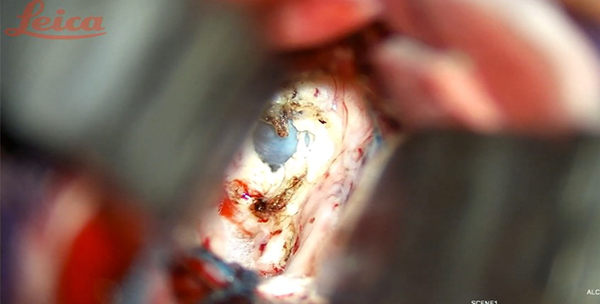

Figura 5. Imagen transoperatoria: realizada la callosotomía se aprecia lesión quística* descrita.

Se procede con la microdisección circunferencial del quiste bajo visión directa, en última instancia en sentido posterior separándolo del plexo coroideo y demás estructuras neurovasculares a lo largo del techo del tercer ventrículo, logrando su exéresis en bloque. La apertura del quiste y succión de su contenido es favorable para la descompresión y movilización de la cápsula con un microdisector para, finalmente, con pinza de biopsia realizar la exéresis en bloque. Debe prevenirse la manipulación del fornix y cuidar que la succión no dañe las estructuras circundantes. Las cavidades ventriculares se irrigan evacuando cualquier residuo. Una vez alcanzada la hemostasia, la duramadre se cierra de forma hermética y se sutura por planos según técnica habitual. Puede ser necesario dejar un catéter ventricular el cual será retirado en el período postoperatorio. En el presente caso se mantuvo por 72 horas.